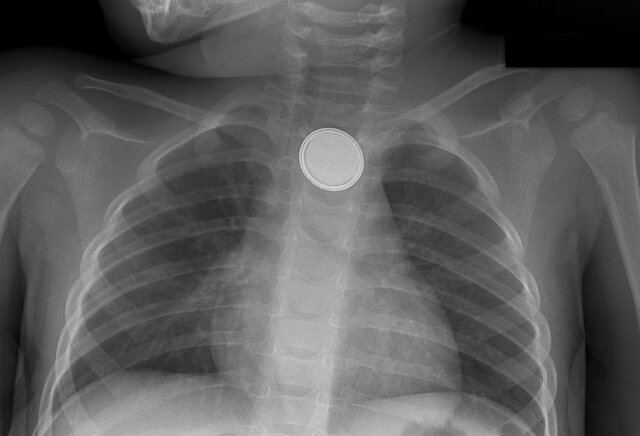

باتریهای دکمهای که قطر آنها ۲ سانتیمتر یا کمتر است معمولا در طیف وسیعی از لوازم مانند اسباب بازیها، ساعتها و سوئیچهای الکترونیکی استفاده میشوند و به اندازهی کافی کوچک هستند که کودک بدون اینکه متوجه شود آن را ببلعد. هنگامی که باتری وارد مری میشود، شروع به فعل و انفعالاتی با مایعات محیط [مری] میکند و جریان الکتریکی را سبب میشود که واکنشهای شیمیایی خطرناکی را در پی دارد.

پس از رسیدن کودک به بیمارستان، ابتدا بررسی میشود که آیا باتری هنوز در مری گیر کرده است یا خیر سپس با استفاده از آندوسکوپ (Endoscope) باتری خارج میشود.